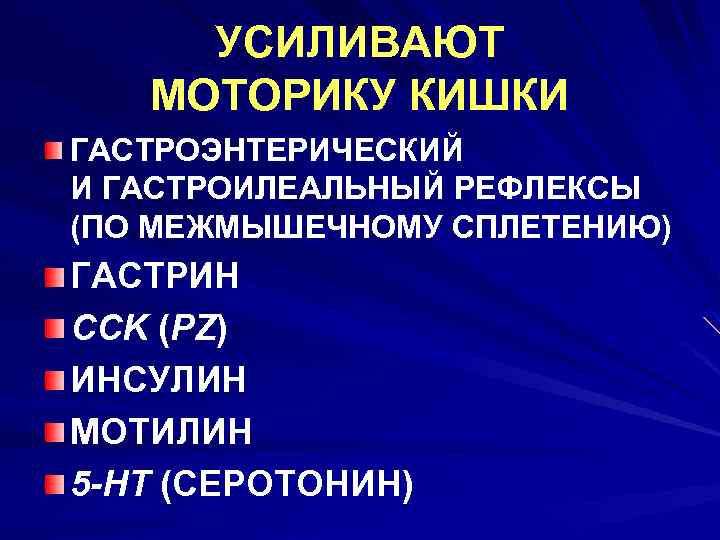

УСИЛИВАЮТ МОТОРИКУ КИШКИ ГАСТРОЭНТЕРИЧЕСКИЙ И ГАСТРОИЛЕАЛЬНЫЙ РЕФЛЕКСЫ (ПО МЕЖМЫШЕЧНОМУ СПЛЕТЕНИЮ) ГАСТРИН CCK (PZ) ИНСУЛИН МОТИЛИН 5 -HT (СЕРОТОНИН)

УСИЛИВАЮТ МОТОРИКУ КИШКИ ГАСТРОЭНТЕРИЧЕСКИЙ И ГАСТРОИЛЕАЛЬНЫЙ РЕФЛЕКСЫ (ПО МЕЖМЫШЕЧНОМУ СПЛЕТЕНИЮ) ГАСТРИН CCK (PZ) ИНСУЛИН МОТИЛИН 5 -HT (СЕРОТОНИН)

ТОРМОЗЯТ МОТОРИКУ СЕКРЕТИН ГЛЮКАГОН

ТОРМОЗЯТ МОТОРИКУ СЕКРЕТИН ГЛЮКАГОН